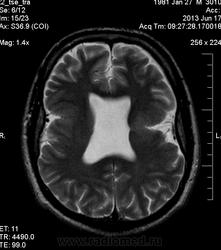

Мужчина 32 лет. Из анамнеза: перинатальное повреждение ЦНС, ДЦП, дизартрия, правосторонний верхний монопарез. С 16 лет приступы эпилепсии.

Аплазия прозрачной перегородки. Шизэнцефалия с открытыми краями в лобно-теменной области слева. Шизэнцефалия с закрытыми краями в лобной области справа? Утолщение коры по контуру расщелин и в области глазничной извилины правой лобной доли. Микрогирия? Гиперостоз костей свода черепа. Уважаемые коллеги, возможно я ошибаюсь, или есть еще аномалия?

сочетания отсутствия прозрачной перегородки и дисплазии ( разно степени выраженности) зрительных неровов  указывает на септоптическую дисплазию-нарушение развития в области средней линии , сопровождается мнггими другими структурными аномалиями, чаще шизэнцефалией.

На мой взгляд, полимикрогирия двусторонняя (конвекситальные отделы дорзальных отделов лобных долей и частично теменных, а также в базальном отделе полюса правой лобной доли) + закрытая шизенцефалия левой лобно-теменной области. Аплазия прозрачной перегородки (как признаки лобарной голопрозенцефалии).